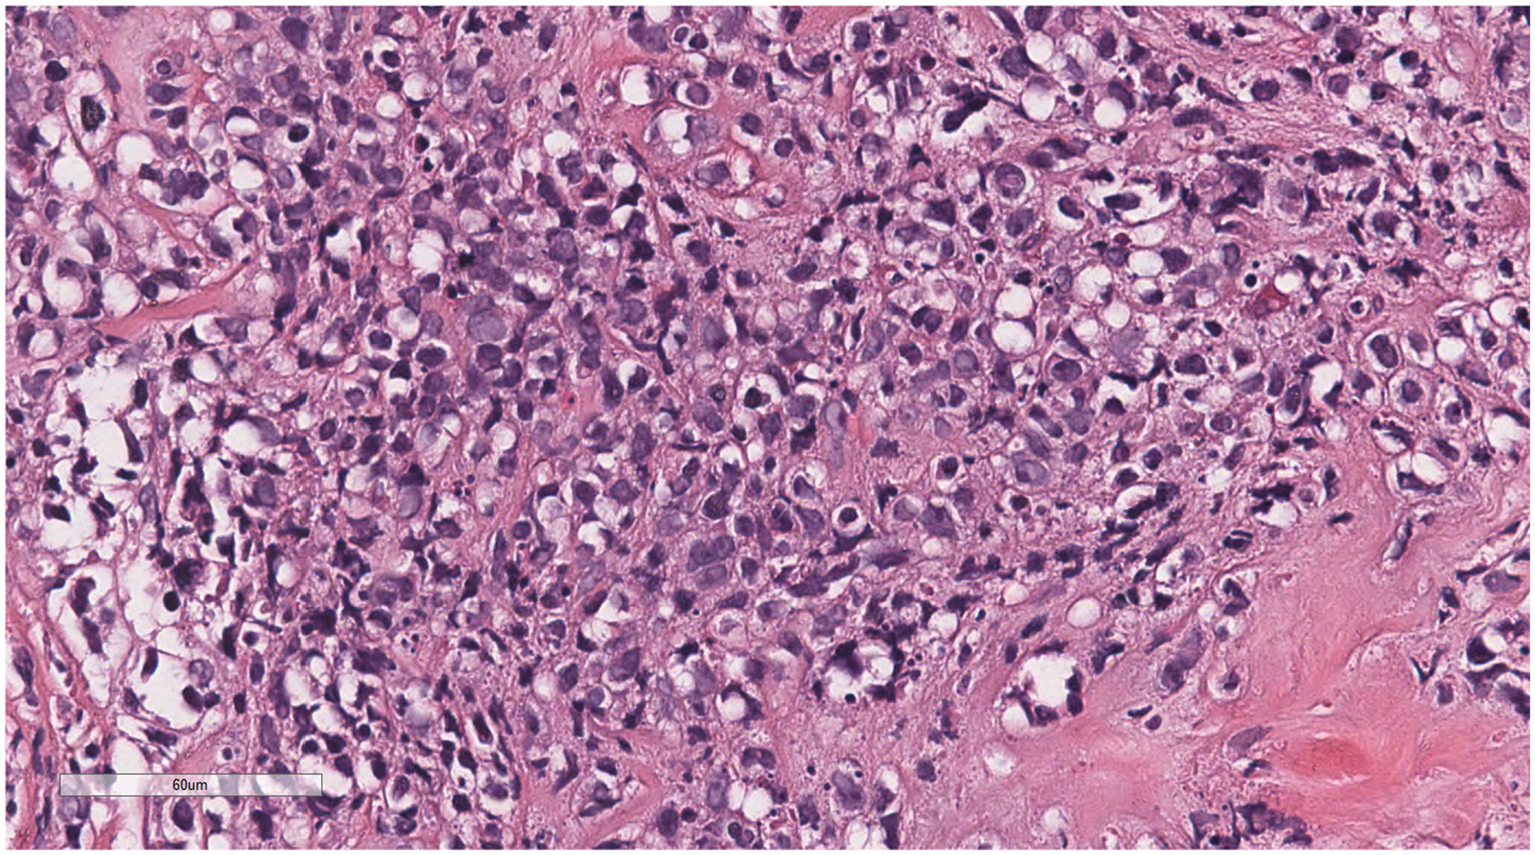

Microscopically (Figures 2–8), the breast biopsy tissue revealed diffuse proliferation of lymphocyte-like cells arranged in cords or nests, which infiltrated the breast stroma and surrounding fat. At medium magnification, patches of mononuclear cells with loose arrangements and uniform dispersion were observed. Some of these cells were arranged in a linear or nonpiled pattern, with slender fibrous septa visible. The cells were medium to large, with indistinct nucleoli, primitive to folded nuclei, fine chromatin, scattered eosinophils, and mitotic figures. Some of the cells were medulloblastoid, with scant cytoplasm, round nuclei, and small nucleoli. Some of the cells were myelomonocytic or monocytoid, with local fibrous tissue proliferation.

Figure 7

The cells were medium to large, with unclear nucleoli, the nuclei were primitive to folded, the chromatin was partially empty and bright, and there was local fibrous tissue proliferation.

Figure 8

Some of the cells were medulloblastoid, with scant cytoplasm, round nuclei, and small nucleoli.